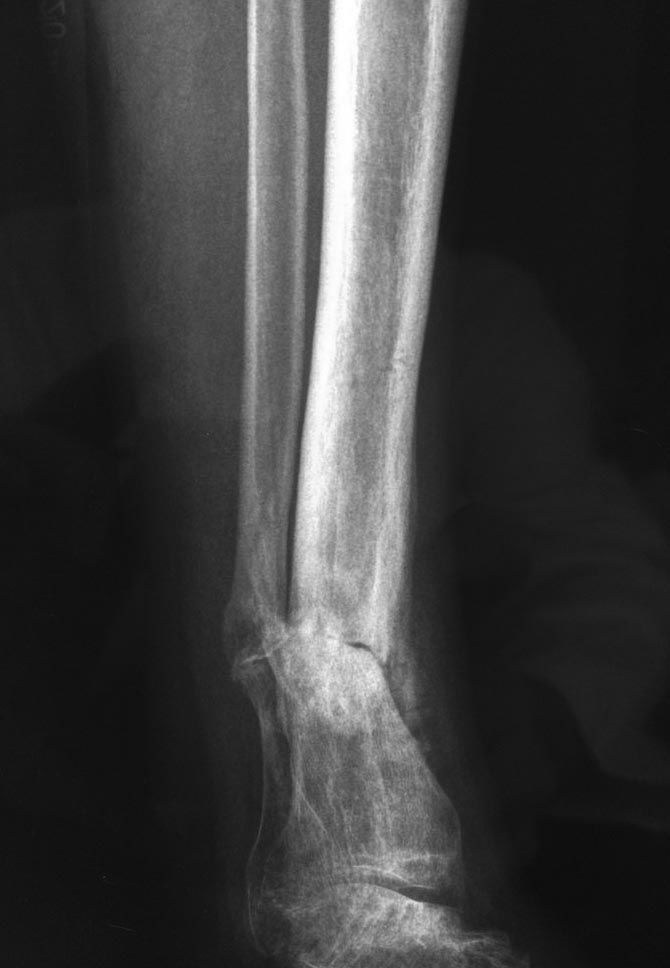

Уважаемые коллеги выразите Ваше мнение по следующему случаю.Молодой человек, 27 лет, находится на лечении с диагнозом: Ложный сустав большеберцовой кости в нижней трети, фиксированный интрамедуллярным блокированным стержнем (12.02.2014 г), ложный сустав малоберцовой кости в нижней трети левой голени, посттравматический артроз левого голеностопного сустава 1 стадии. Укорочение левой нижней конечности на 1,0 см. Со слов пациента известно, что в детстве получил перелом большеберцовой кости, лечился консервативно, перелом сросся с деформацией. Травма в июле 2010 г. бытовая-упал на лестнице, получил перелом малоберцовой кости, и перелом большеберцовой кости без смещения. Выполнена операция: Остеотомия большеберцовой кости в нижней трети, интрамедуллярный блокированный остеосинтез большеберцовой кости левой голени. Гладкое течение послеоперационного периода. Перелом большеберцовой кости сросся. Функция конечности восстановилась. В июне 2013 г выполнена операция удаление интрамедуллярного стержня из большеберцовой кости левой голени. Гладкое течение послеоперационного периода. Приступил к занятием физкультурой, бег. В августе 2013 г спрыгнул с автобуса, с чемоданом в руках, появилась резкая боль в левой голени. За медицинской помощью обратился через 7 дней, при обследовании выявлено: Рефрактура большеберцовой кости. Рекомендовано консервативное лечение в гипсовой повязке. В январе 2014 г. установлен диагноз: Ложный сустав большеберцовой кости в нижней трети, малоберцовой кости в нижней трети левой голени. Контрактура сгибательно - разгибательная левого голеностопного сустава. Посттравматический артроз левого голеностопного сустава 1 стадии. Укорочение левой нижней конечности на 1,0 см. В феврале 2014 г выполнил первым этапом: Фиксацию ложного сустава в АНФ с восстановлением осей сегментов. Через семь дней БИОС с рассверливанием. После операции - вальгус голеностопного сустава. Гладкое течение послеоперационного периода. Нагрузка по переносимости боли. Через 6 недель динамизация, через 2 недели стали мигрировать 2 фронтальных винта. Пытался подкрутить, пришлось удалить. Через 6 мес., контроль - линия ложного сустава прослеживается, но имеется периостальная костная мозоль. Не хватает стабильности.Вопрос что делать?Вариант № 1- выполнить реостеосинтез с рассверливанием КМК и на 12 мм диаметра гвоздь (стоит 11 мм)и убрать ротацию стопы руками одномоментно или одномоментно при помощи АНФ во время операции. Вариант № 2 выполнить удаление гвоздя, сделать все то же, что 6 месяцев назад, но с восстановлением анатомических взаимоотношений в голеностопном суставе.Вариант № 3 Двухэтапно, вторым этапом пластина на большеберцовую кость + костная пластика области не сращения.Вариант № 4 удаление гвоздя и лечение в КДА. Вопросы:1. Какой вариант оперативного лечения будет оптимальным в данном случае.2. При двухэтапной методике в дистальном отломке имеется канал от гвоздя, как направить гвоздь к наружному отделу дистального отломка большеберцовой кости. Есть опасения, что гвоздик может пойти по тому же каналу. Использовать поллер спицы или винты – сработают ли? И достаточна ли будет жесткость фиксации дистального отломка большеберцовой кости на гвоздике при 3 – 4 винтах при реостеосинтезе гвоздем.3. Нужен ли остеосинтез малоберцовой кости в нижней трети, с целью создания латеральной опоры. К сообществу за советом.

Здесь можно использовать все названные варианты. Гвоздь вполне тоже можно. Надо аппаратом восстановить длину и не повторять прежней ошибки - надо латеральную стенку сопоставить, а не оставлять наружного смещения. Да, надо ввести передне-задние спицы, чтобы не дать стержню попасть в старый канал. И длинной ручной разверткой лучше бы сформировать новый канал.

Возможно, не все снимки выставлены, потому что не нашел признаков проведенной динамизации, о которой писали. Верхние винты остались нетронутыми, трудно опознать динамизацию. По поводу применения “cap” на гвозде имеется сомнение, потому что высоко расположенный по верхнему краю гвоздь не позволяет воспроизвести динамизацию. Перед динамизацией надо укорачивать гвоздь или убирать “кап”.

По поводу лечения, проблем правильной установки гвоздя не будет. Можно с помощью поллеров, которые помогут вывести в нужную траекторию. Но, если прежние попытки не привели к успеху, стоит ли тогда повторить неудачный опыт? Какая гарантия, что вальгусные силы не деформирует ось. Надо пересмотреть иллюзию, что гвоздь является идеальным фиксатором для решения данной патологии! Еще, при попытке подвести проблему под определенный фиксатор, результат получается неутешительным!

Из предложенных, я бы остановился на третьем варианте. Основная работа должна быть против вальгуса, и медиальная пластина для этой роли не подходит. Передний доступ, остеотомия большой и малоберцовой. Сагиттальная пила для артропластики толстая и не экономит кость. Полотно не более, чем 1.1 мм толщиной, создает идеальную поверхность остеотомии. Затем боковая компрессия-лагированием и передная пластина с костным графтом! Возможно, потеряет часть высоты, но наконец то возникнет сращение!